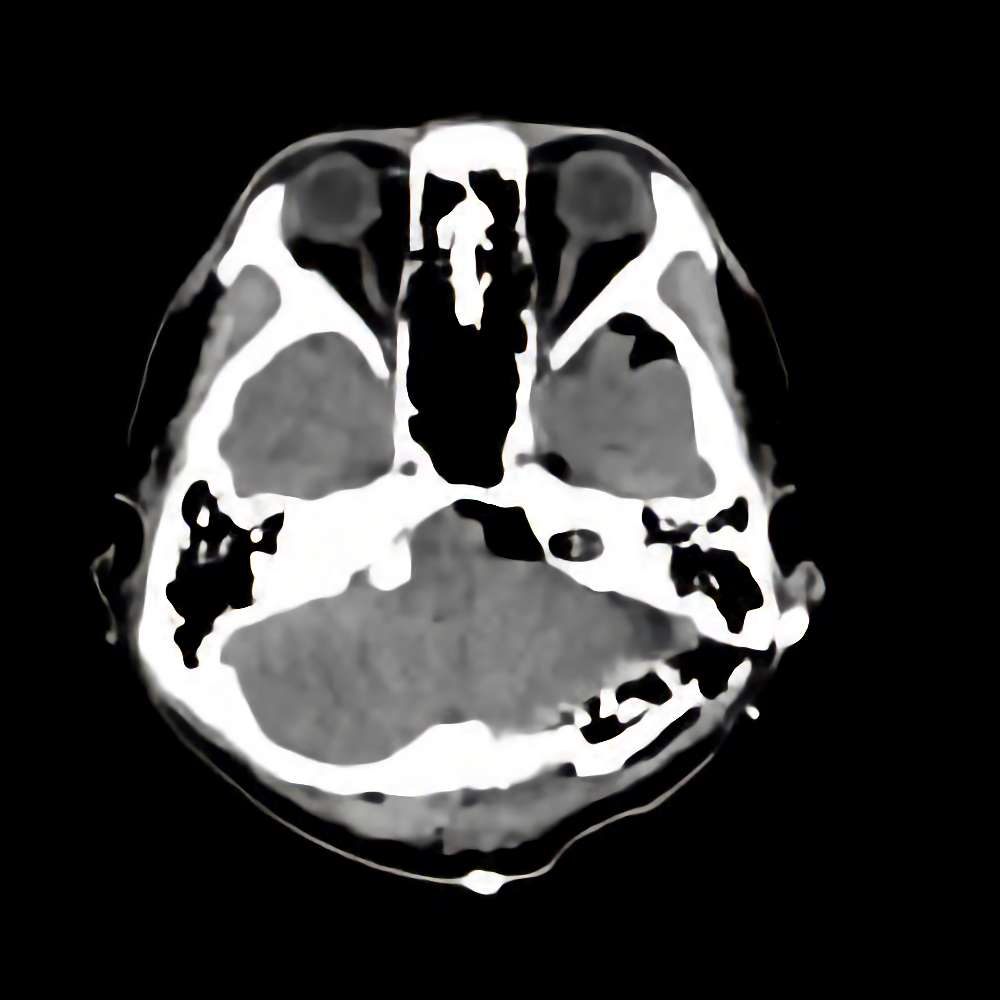

218

'21年9月

80代

左後頭頂葉腫瘤

頭蓋内腫瘍摘出術